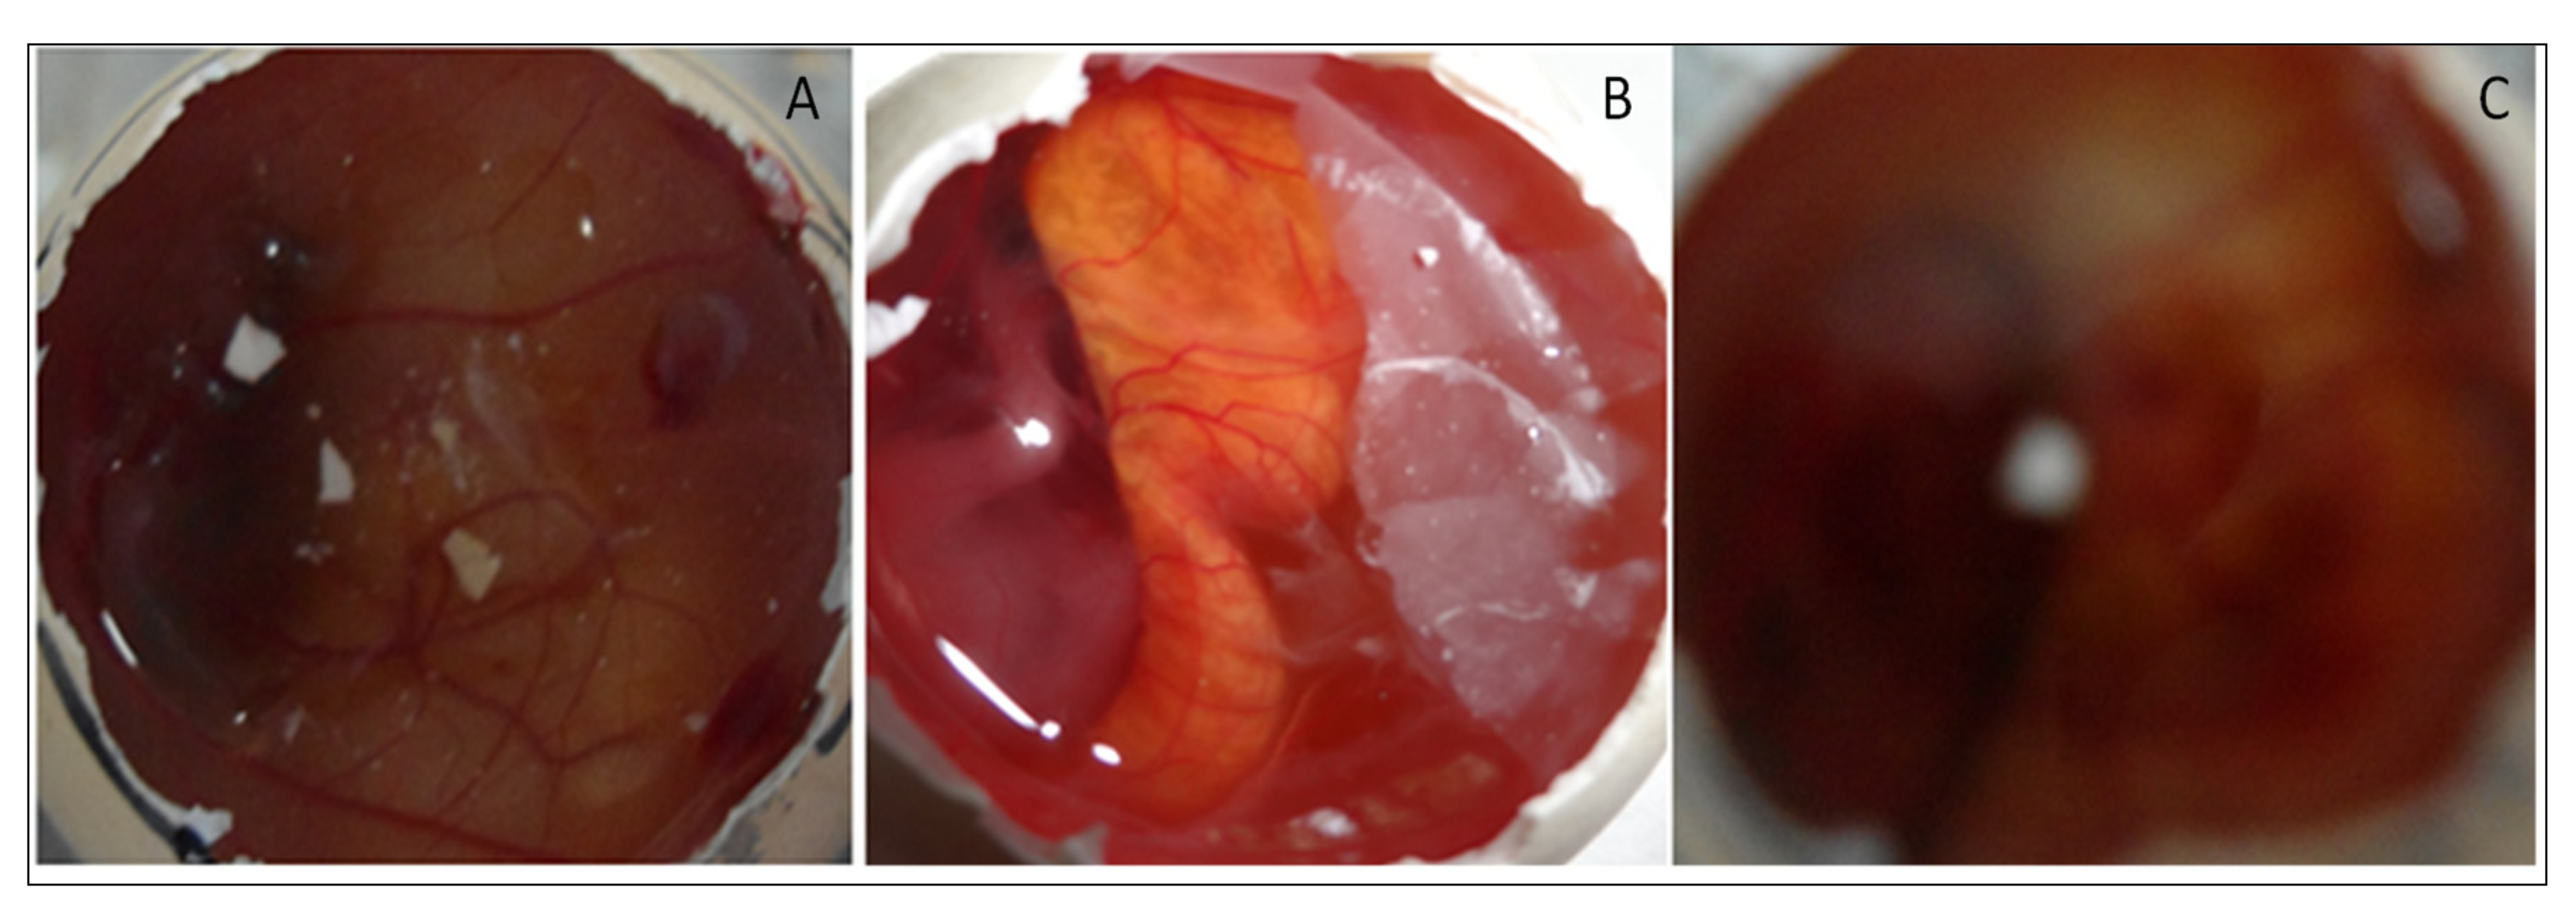

HET-CAM (irritation) study was performed for EM-NLCs-opt-IG4, normal saline (0.9% NaCl, negative control) and positive control 0.1N sodium hydroxide) using a fertilized hen egg’s (Figure 8). The developed CAM after incubation is similar to the artery and vein of an eye. EM-NLCs-opt-IG4 and normal saline-treated CAM showed no irritation. There was no haemorrhage and bleeding from the artery and vein of CAM (no breaking) observed in 5 min. and the score was found to be closer to zero. In addition, the positive control (0.1N NaOH) treated CAM depicted a score of 6 and indicated haemorrhage of artery and vein of CAM in 5 min. So, the positive control treated CAM is considered a severe irritant. The study revealed that the developed EM-NLCs-opt-IG4 formulation was found to be non-irritant and safe for ophthalmic administration.

Figure 8.

HET-CAM image of (A). EM-NLCs-opt-IG4, (B). Negative control (0.9% NaCl) and (C). Positive control (0.1 N NaOH).